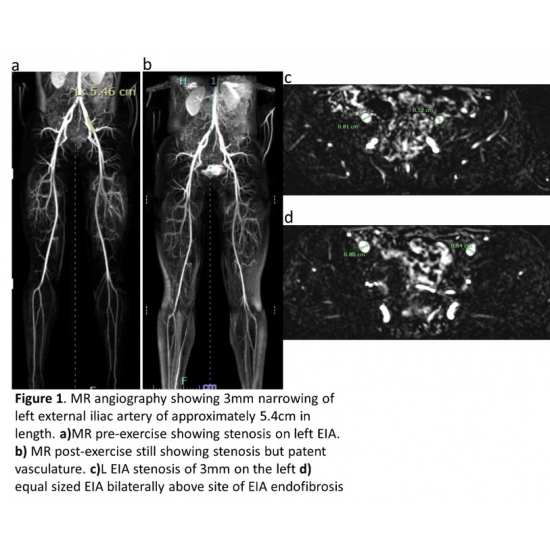

| A Rare Cause Of Unilateral Leg Pain In A Competitive Triathlete - Page #3 | |||